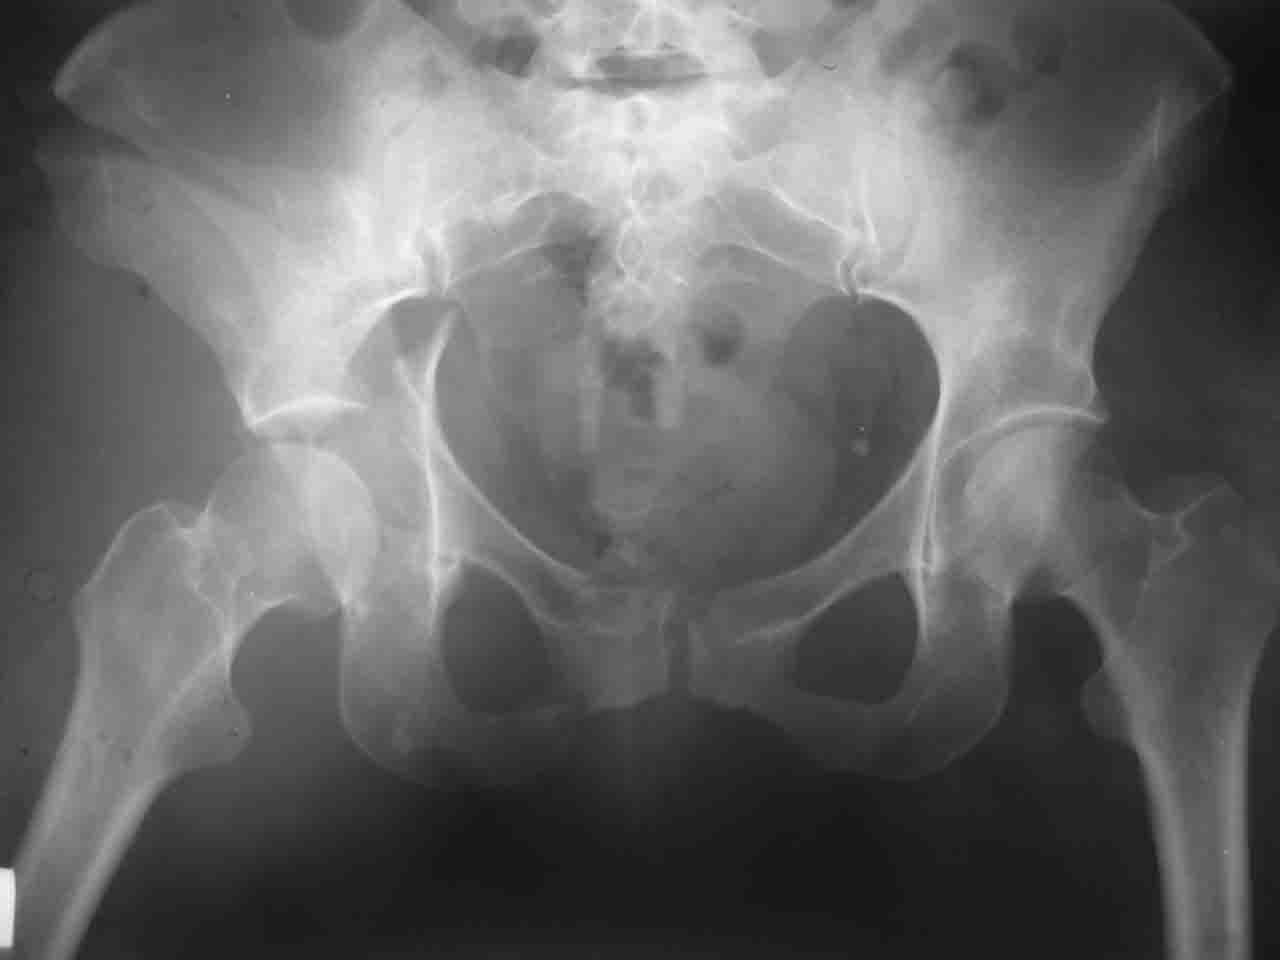

Интерес к реконструкции вертлужной впадины у меня появился довольно-таки давно, но до недавнего времени как-то не ощущалась готовность к практической реализации, а местный подход достаточно консервативен - перелом срастется,

а далее будет видно. Такую точку зрения я не разделяю, поэтому через конференции,ортофорум и свои случаи пытаюсь практически и теоретически *продвинуть* для себя тему реконструкции вертлужной впадины.

Логика подсказывает, что все-таки лучше иметь анатомически полноценную впадину, хотя ранее упоминалось состояние вторичной конгруэнтности и одно наблюдение у меня есть, когда у больного с полностью нарушенной анатомией впадины и подвывихом головки бедра кзади и кверху боли отсутствовали при относительно достаточном для стиля жизни больного объёме движений. Но это только одно наблюдение и кроме перелома впадины у этогобольного была и тяжелая ЧМТ в анамнезе. Основываясь на формулировке структуры ацетабулюм Э. Летурнеля - как перевернутой буквы Y, впадина для полноценной функции сустава должна иметь сферичность, соответствующую размеру головки бедра и если один из компонентов в дефиците, то функциональные последствия рано или поздно проявятся.

Сложностью, ассоциативностью характера перелома, я бы с радостью воспользовался мининвазивной перкутанной фиксацией винтами, но боюсь, что результат был бы ещё хуже, техникой непрямой репозиции перелома не владею, поэтому пытаясь получить анатомичную впадину приходится широко открывать, по крайней мере пока, а дальше буду пытаться уменьшать пространство...

Илеофеморальный доступ не совсем передний и сравнительно с илеоингвинальным, и Кохера-Лангенбека открывает весь наружный таз кроме самых передних отделов лонных костей, фиксацию которых я не ставил в задачу. Обширность диссекции, большая длительность операции и более высокий риск гетерооссификации - отрицательные моменты в обмен на возможность легче ориентироваться.

Комбинированные доступы - хорошая альтернатива, меньший процент осложнений, но я заметил , что без сбора *мозаики* безымянной кости сложно отрепонировать переднюю колонну, а с нерепонированной передней колонной невозможно анатомично собрать заднюю колонну и соотв. фрагменты стенки - так.что все равно открывать придется широко. Поэтому выбирая комбинированный

подход, передний доступ должен был бы быть продлен до задней трети крыла безымянной кости, а задний - практически до того же уровня, оставляя 6-7 см мостик. При этом вместо одного послеоп. рубца у больного остаются два сравнительно длинных.

Вопрос доступа к вертлужной впадине при остеосинтезе задача не простая. Конечно, у Летурнеля и Тайла всё давно описано, нам остается только брать на вооружение. Но сами понимаете, что не бывает двух одинаковых ситуаций, поэтому в каждом случае вопрос решается сугубо индивидуально. Наша главная цель - восстановить анатомию с нанесением минимальной дополнительной травмы тазобедреннному суставу, думаю с этим никто не поспорит. Расширенный илиофеморальный доступ уж слишком травматичен (как сказал один коллега "таз лежит отдельно, больной отдельно").Стоит ли делать из пациента анатомический препарат для того чтобы легче ориентироваться. Да и нужно ли собирать всю "мозаику"? Мы применяли при таких операциях своеобразную операционную хитрость - сначала устраняли грубое смещение крыла под гребнем с фиксацией так называемой "плавающей" пластиной (временно фиксированной на двух винтах)- доступ или продлевали боковой, или делали небольшой дополнительный разрез над гребнем. Это позволяло устранить грубое смещение и захождение отломков тела повздошной кости, что значительно облегчало репозицию и остеосинтез впадины над сводом. Основное внимание конечно же уделяли нагружаемому задне-верхнему отделу. Сообщите ваш адрес, пришлю схемы и рентгенограммы.